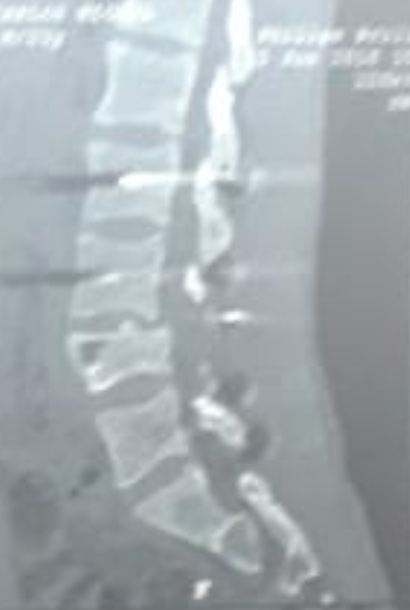

Figura 3.

Caso 1. Tomografía computarizada, corte sagital.

El paciente es trasladado al Servicio de Urgencia del hospital regional y, de allí, es derivado a nuestro centro, a través de su obra social. Ingresa, reactivo, lúcido (escala de Glasgow 15/15), con estabilidad hemodinámica y síndrome de cauda equina incompleto (grado B según el puntaje de la ASIA).19 Se solicitan radiografías y TC de columna cervical, torácica y lumbosacra. Se constata fractura vertebral lumbar baja con compromiso de la cuarta vértebra lumbar (L4), de tipo estallido, con retropulsión de un fragmento voluminoso del muro posterior en el canal, con impronta en el saco dural. La resonancia magnética no mostró una lesión del complejo ligamentario posterior, por lo que se interpreta, según la clasificación AO, como L4: A3, N3, M0 (Figuras 2 y 3). Sin deformidad en cifosis significativa y con un colapso vertebral inferior al 50%. Se constata una lesión hepática asociada, se lo somete a una laparotomía de urgencia y queda internado en la Unidad de Terapia Intensiva.